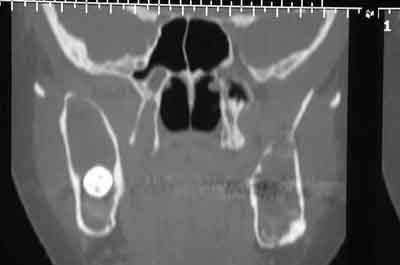

Femme de 40 ans. Aucun antécédent (notamment chirurgical) en dehors d'un DNID, d'un tabagisme modéré (5 paquets-année) et d'une surcharge pondérale. Consulte pour apparition progressive d'une volumineuse voussure dans les 2 vestibles inférieurs et d'une modification consécutive de la forme de la partie inférieure de son visage. A l'examen clinique : tuméfaction dure et fixée dans les 2 vestibules. Sensibilité (V3) normale. Gencive normale. Dents restantes non mobiles, vitales. Pas d'adénopathies palpables. Biologie non faite pour l'instant. Je vous joinds l'OTP et le scan. Diagnostic et options de traitement?

du coté de la dent incluse dans le ramus, on peut penser comme diagnostic probable a un kyste d'origine dentaire -image uniloculaire bordée sur son pourtour par une corticale bien individualisée et sur le scanner disparition de l'espace péricoronaire de la couronne avec continuité de toute la cavité.

diagnostic différentiel a faire avec d'autre lésions par ponction et anapat qui confirmeront ou non le diagnostic présomptif.

on peut penser a une tumeur de Pindborg, les pourtours des cavités sont moins nettes et rondes que pour un améloblastome et de plus la tumeur a des bords irréguliers et une tendance à l'envahissement local qui semble confirmé par la disparition de la corticale supérieure sur la partie coronaire de la mandibule

localisée à la mandibule...image radiographique claire en rapport avec une dent incluse qui est refoulée...il existe ici de multiples géodes...présence de calcifications dans la clarté...

Bref, en ce qui concerne ce cas (assez récent), je vous livre le raisonnement qui a été le notre : probables kystes péricoronnaires sur les dents incluses (il n'y a pas de dents "surnuméraires"...). Décision d'abord chirurgical pour énucléation des 3 kystes (les ponctions ne "marchent" pas dans ces lésions) et examens anatomopathologiques extemporanés pour décider, en per-opératoire, de la conduite à tenir (photo 1).

Diagnotic extemporané : kératokystes (!). Les dents incluses se sont donc avérées être un piège diagnostic! Le traitement s'est de ce fait contenté d'un curetage appuyé des paroies osseuses, conservation des 2 nerfs dentaires et, en raison de la taille des kystes mandibulaires et du risque de fracture post-opératoire, nous avons y avons associé une greffe (hydroxyapatite + os autologue (crête illiaque) + PRP) au niveau mandibulaire uniquement (photos 2 et 3)et blocage intremaxillaire pendant 15 jours.